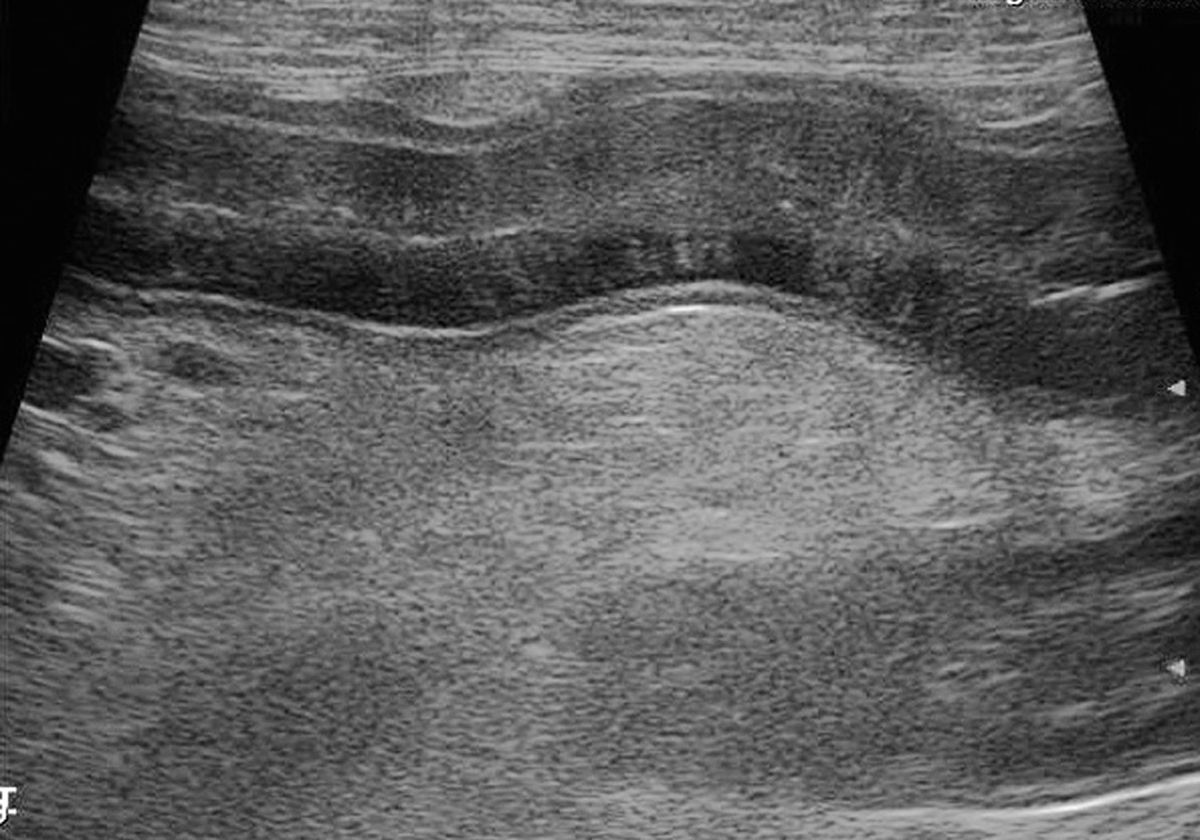

From www.mspca.org

Small Intestinal Disease on Ultrasound • MSPCAAngell Dog Food For Intestinal Lymphangiectasia If the underlying condition is treatable then prognosis for lymphangiectasia is good, but. Lymphangiectasia in dogs is an intestinal disease where a disruption to the lymphatic system results in loss of fats and. Lymphangiectasia is an intestinal disease whereby the lymphatic fluid of the body is leaked into the gastrointestinal tract. The goal is to eventually return to a standard. Dog Food For Intestinal Lymphangiectasia.